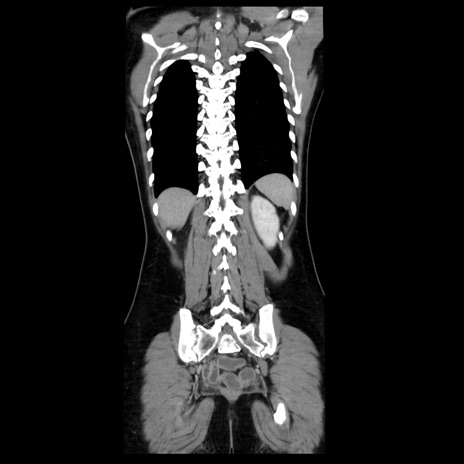

CT